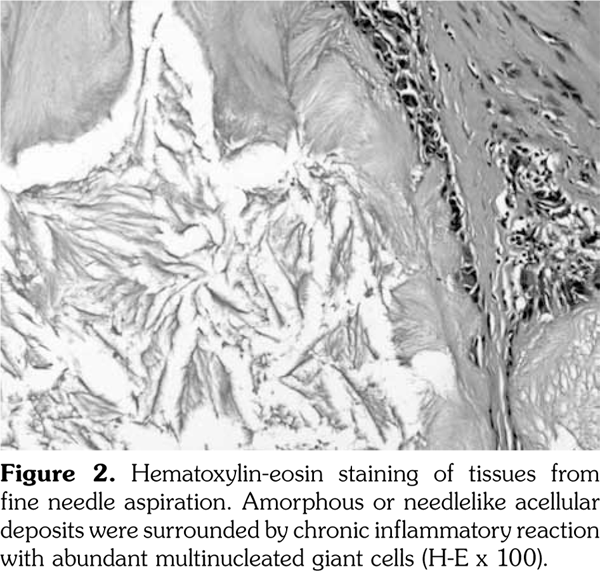

A 54-year-old male patient was admitted to our department with palmar numbness and disability for two years. He had a history of gout for 30 years but received no treatment. Physical examination revealed obvious subcutaneous tophi and thenar muscle wasting. Flexion deformity of his metacarpophalangeal and interphalangeal joints is shown in Figure 1a. Positive Tinel’s sign and Phalen’s maneuver were present. Routine laboratory test showed high level of uric acid (608 μmol/L). The electrophysiological examination revealed sensory and motoring demyelinating and axon lesions in both median nerve, especially in the right hand, which supported the diagnosis of CTS. Furthermore, DECT showed extensive monosodium urate crystals in the intercarpal and radiocarpal joints with compression overlying the flexor tendons (Figure 1b, c). We also observed punched-out bony erosions in the carpal bones (Figure 1d). These aspects indicated severe and typical CTS caused by gouty tophi, which was further confirmed by biopsy of fine-needle aspiration (Figure 2). Surgery was recommended, but the patient refused to undergo surgery and chose to receive febuxostat. Uric acid level had decreased in the next six-month follow-up with little improvement for his numbness and deformity. A written informed consent was obtained from the patient.